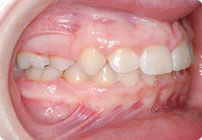

Caso: 11 años

Adolescente: Clase II

Mordida Cruzada Posterior

Sin extracción

Sin uso de expansores

6 alambres superiores

5 alambres inferiores

Sin uso de elásticos

Retenedores: Interior Fijo de TMA y Hawley en superior

Tiempo de tratamiento: 14 Visitas